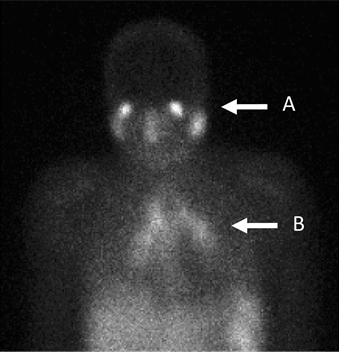

Gallium tends to concentrate in areas of the body where there is rapid cell division. This is seen on pictures taken with the gamma camera. Where large amounts are seen, this can be a sign of infection, inflammation, injury or possible cancer. The image below shows how sarcoidosis may be diagnosed by gallium scan.

Gallium scan image

By A B Allard, J Buscombe, D P Kidd [CC BY-SA 4.0], via Wikimedia Commons

Diagnose inflammatory conditions such as pulmonary fibrosis or sarcoidosis - as image above.